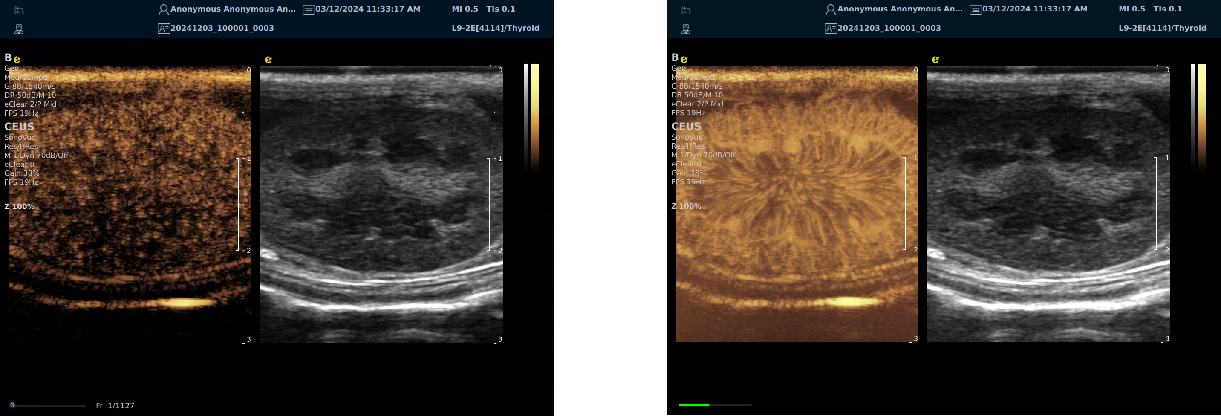

实时剪切波弹性成像

评估组织的软硬,并且提供定量数值,从而提示组织的良恶性。

鉴别诊断、精准分级、定量评价、穿刺引导、疗效评估、随访观察

image.png

恶性占位常常向周边组织进行侵润及扩散,二维很难观察到浸润部分的边界。使用实时剪切波成像能够对占位及周边组织进行硬度评估,通过颜色编码来区分不同组织的硬度信息,直观的观察占位组织的边界信息,更方便区分占位组织和正常组织的边界,准确评估消融范围。

左图病例所示:

钼靶阴性,B型发现非肿块病变

剪切波弹性成像见明确的硬度增高区域。

穿刺及手术病理结果:浸润性导管癌(IDC)

非肿块型病变:B型图像无法确认病变范围,E成像帮助发现异常区域和评估